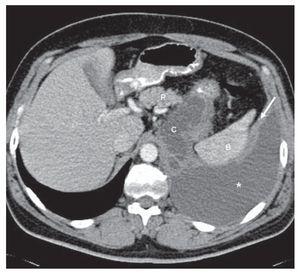

Derrame pleural masivo secundario a pseudoquiste pancreático

Salinas Lasa, Iturbe Susilla, Díaz Urquizo, Ponce Sánchez, Bustamante Madariaga, Crespo Notario

Revista de Patología Respiratoria 2011;14:104-5

Acceso a texto completo